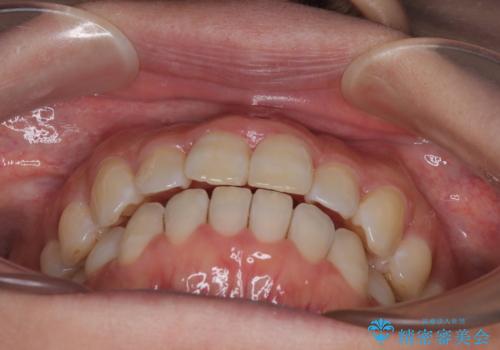

【モニター】飛び出した上顎前歯 補助装置を併用したインビザライン矯正治療

- 上下前歯が非接触となり、前方に突出していることを気にして来院された患者様です。

上下の前後差が大きいため、インビザライン単独での上顎歯列移動は困難と判断し、補助装置により上顎歯列を後方移動させ、その後インビザラインにて仕上げていくこととしました。

補助装置なしでも改善できる可能性はありましたが、補助装置で確実性を上げ、短期間できっちりと仕上げることができました。